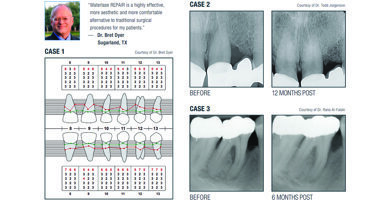

Case II

A female patient presented complaining mainly about her rotated upper right central tooth. She was considering veneers to redistribute the space over the four front teeth. This would have meant that she would undergo three aggressive preparations and one invasive preparation with endodontic treatment of the upper right central tooth.

Space calculation with model analysis indicated that treatment would be possible with an Inman Aligner. Because of the relatively low cost, the patient selected this option, understanding that we would not be able to achieve Golden Proportion, owing to the width and length of her lateral teeth.

A midline screw was incorporated to allow for a small amount of operator-controlled expansion to provide a little more space. (Incorporated expanders can be used to release extra space in cases with very constrained space.) Up to 2 mm of space can be created by expansion, which has the effect of pushing the cuspid away from the lateral.

After alignment, this expansion will just relapse. It is a temporary technique to create sufficient space to align the anterior teeth. After alignment, the expander can even be unwound if required.

Treatment took 13 weeks with three sessions of IPR. A total of 3 mm was stripped and 1 mm was gained with the expander. The teeth were retained using orthodontic gold chain bonded from canine to canine. An upper Essix Retainer was also worn nightly as back-up for retention.

Case III

The patient in this case originally presented for porcelain veneers on her upper anterior teeth. The preparations would have required root-canal treatment of two of her incisors in order to achieve adequate emergence profiles.

After case options had been discussed in detail, the patient decided upon an Inman Aligner to align the teeth with veneers following this treatment. The patient was aware that after alignment, retention would be mandatory. Spacewize arch analysis calculated only 0.8 mm crowding in deviation from the ideal curve.

An upper Inman Aligner with combined expander was fabricated and fitted. Minimal IPR was carried out with a 0.1 mm reproximation strip to separate the teeth. The patient turned the screw every five days for six weeks, which created nearly 2 mm of space.

This allowed space for the centrals to advance and de-rotate. At this point, the expander was unwound to ensure that any mild residual spacing had closed. The teeth were aligned within nine weeks. An Essix Retainer was used to retain the teeth passively for a further four weeks, after which a bonded wire retainer was placed.

The patient was very pleased with the alignment and decided that she would not need veneers. Veneers could always be used at a later stage if necessary, after more enamel has eroded with age and when veneers can be placed additively, for example.

The result was not a perfect smile with regard to the criteria defined by Smile Design theory. Yet, that she no longer wanted veneers arguably provides us with a far better and more ethical outcome long term.